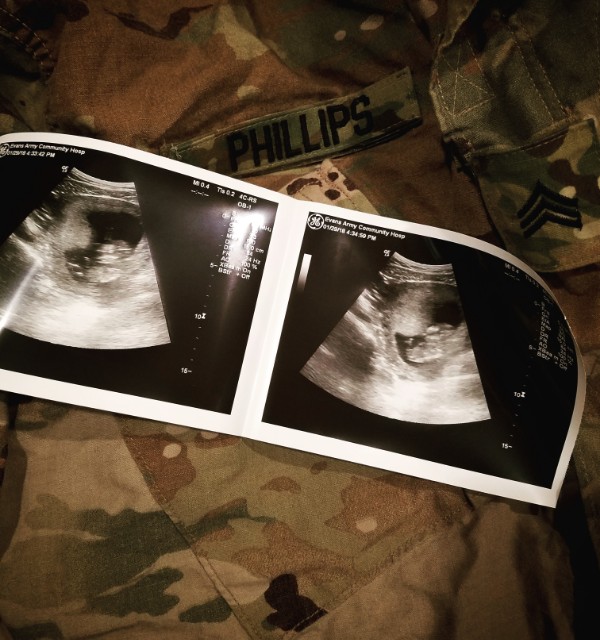

gender guesses ?! im so bad at looking at ultra sounds lolol 12 weeks and a few days!